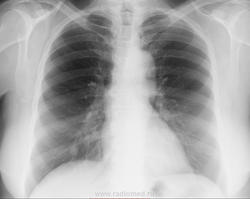

Снимки из серии "найти на боковой". Женщина 1948 г.р. Жалоб со стороны органов грудной клетки нет.Где тень на боковой проекции? К какому диагнозу склоняетесь? На днях будет ЛТ. ТМГ https://radiomed.ru/sites/default/files/styles/case_slider_image/public/user/16807/2_68.jpg?itok=PMWHQcLH https://radiomed.ru/sites/default/files/styles/case_slider_image/public/user/16807/3_42.jpg?itok=jjhsCDoN ID:46784 Fri, 25/04/2014 - 23:33 #1 алкс Offline Last seen: 10 years 6 months ago Joined: 24.10.2012 - 22:55 Posts: 2915 М.б. тутПриложения: Fri, 25/04/2014 - 23:38 #2 Сольвейг Offline Last seen: 3 years 11 months ago Joined: 05.02.2013 - 20:25 Posts: 2239 Ах, не успела. Тут, еще может в средней доле быть, -установка немного хромает. Рачок периферический, по-видимому, растет Fri, 25/04/2014 - 23:38 #3 NIL Offline Last seen: 3 weeks 1 day ago Joined: 25.11.2013 - 20:50 Posts: 18217 Да. Это она. Судя по гладкости и чёткости контуров, можно думать о доброкачественном новообразовании. Возможно, аденома.Приложения: "Слушай всех, прислушивайся к немногим, решай сам".© Fri, 25/04/2014 - 23:39 #4 Сольвейг Offline Last seen: 3 years 11 months ago Joined: 05.02.2013 - 20:25 Posts: 2239 А почему тмг не сейчас? Не сделали? Fri, 25/04/2014 - 23:57 #5 Dima Offline Last seen: 7 years 8 months ago Joined: 05.08.2012 - 17:39 Posts: 2467 Миргалина wrote: А почему тмг не сейчас? Не сделали?сделал, только карты открывать не хотелось сразу... Терпимость - это когда прощают чужие ошибки; такт - когда не замечают их. (Артур Шницлер) Sat, 26/04/2014 - 00:00 #6 Сольвейг Offline Last seen: 3 years 11 months ago Joined: 05.02.2013 - 20:25 Posts: 2239 Да открывайте уж, интересно же.Пожалуйста! Sat, 26/04/2014 - 00:15 #7 Dima Offline Last seen: 7 years 8 months ago Joined: 05.08.2012 - 17:39 Posts: 2467 Тень там где её и указали коллеги. Глазастые все, молодцы, а я вот долго искал...Приложения: Терпимость - это когда прощают чужие ошибки; такт - когда не замечают их. (Артур Шницлер) Sat, 26/04/2014 - 00:12 #8 Сольвейг Offline Last seen: 3 years 11 months ago Joined: 05.02.2013 - 20:25 Posts: 2239 Ну да, в 10-ке. Спасибо! Sat, 26/04/2014 - 10:03 #9 NIL Offline Last seen: 3 weeks 1 day ago Joined: 25.11.2013 - 20:50 Posts: 18217 Тень плотная. Может оказаться и гамартохондромой. "Слушай всех, прислушивайся к немногим, решай сам".© Tue, 29/04/2014 - 00:37 #10 lady.zhaneta Offline Last seen: 1 year 7 months ago Joined: 06.07.2011 - 21:54 Posts: 232 Спасибо от тех ,кто учится читая ваши комментарии, и от себя лично)

Ах, не успела. Тут, еще может в средней доле быть, -установка немного хромает. Рачок периферический, по-видимому, растет

Да. Это она. Судя по гладкости и чёткости контуров, можно думать о доброкачественном новообразовании. Возможно, аденома.

Тень там где её и указали коллеги. Глазастые все, молодцы, а я вот долго искал...

Ну да, в 10-ке. Спасибо!

Тень плотная. Может оказаться и гамартохондромой.